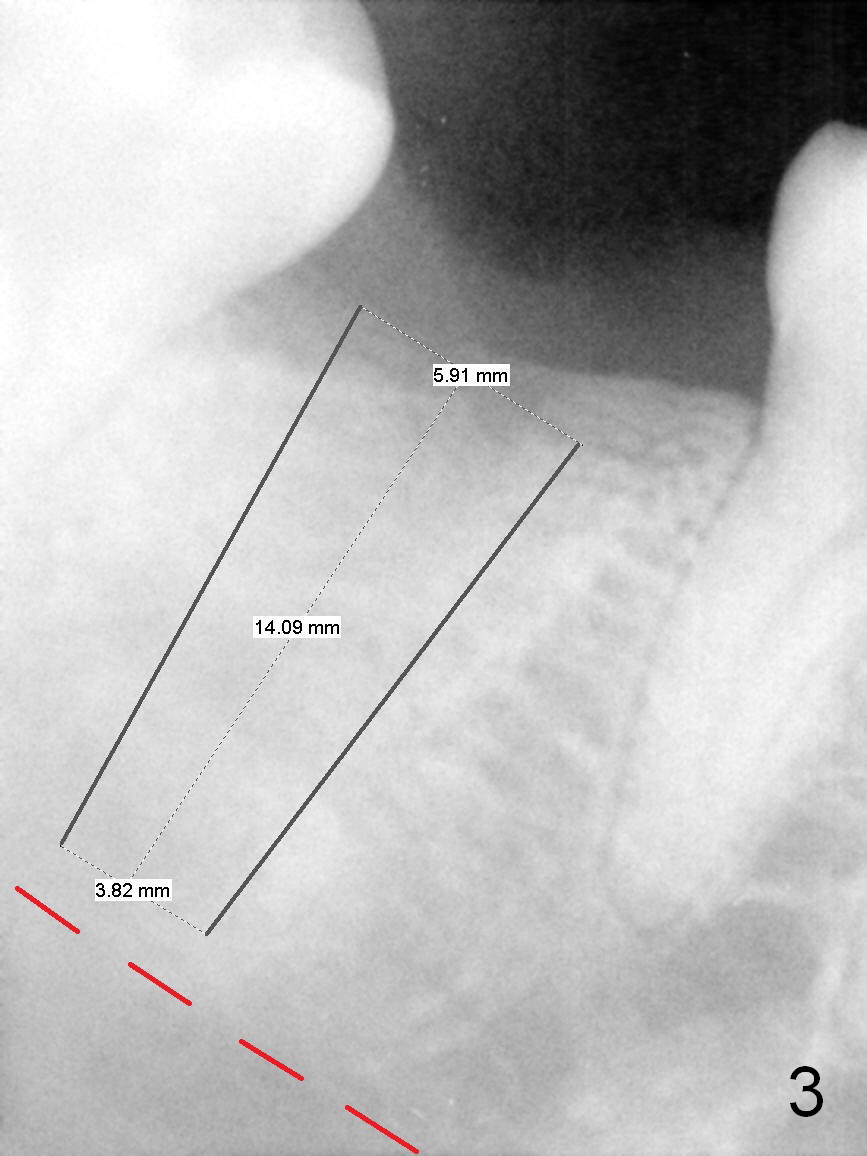

PA in Fig.2 is taken 2 months post extraction, while Fig.3 shows design of a 5.9x14 mm bone-level implant. It appears that the implant is a little too long (red dashed line: the superior border of the Inferior Alveolar Canal). Initial osteotomy depth will be 12 mm. In fact the implant was designed to be supracrestal distal (mistake, even if bone graft is well executed). An incision will be made for visibility.